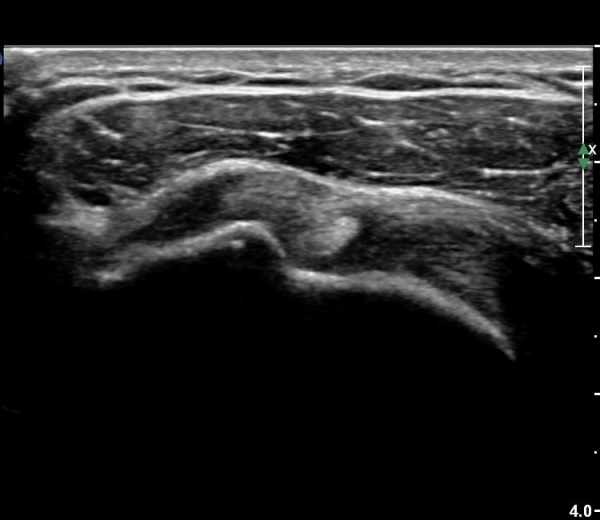

¿À±¸µ¹±â°ßºÀÀδë Á¾´Ü¸é°Ë»ç¿¡¼­ Àδ밡 Á¤»óÀûÀ¸·Î °üÂûµÇ°í(»çÁø 4)

°ßºÀ¿¡ À§Ä¡ÇÑ  ŽÃËÀÚ¸¦ ¾à°£ ¸»´Ü(caudal)À¸·Î À̵¿ÇÏ´Ï °ßºÀ ¾Æ·¡Ãø¿¡¼­ ³»ÃøÀ¸·Î °í¿¡ÄÚ ¼®È¸È­À½¿µÀÌ °üÂûµÈ´Ù(»çÁø 5).